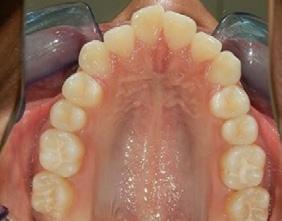

Resultados

Se lograron los objetivos planteados, durante el tiempo de tratamiento de 3 años y 10 meses, en la Figura 11 se puede observar que del lado derecho se obtuvo la clase I molar y se mantuvo la clase III molar izquierda, clase I canina bilateral, la línea media superior coincidente e inferior desviada 0.5 milímetros a la derecha al final del tratamiento, adecuada intercuspidación, en la Figura 12 la forma oval de la arcada superior e inferior.

Figura 10. Vista oclusal superior e inferior. Figura 11. Intraorales finales. Figura 12. Oclusales superior e inferior.